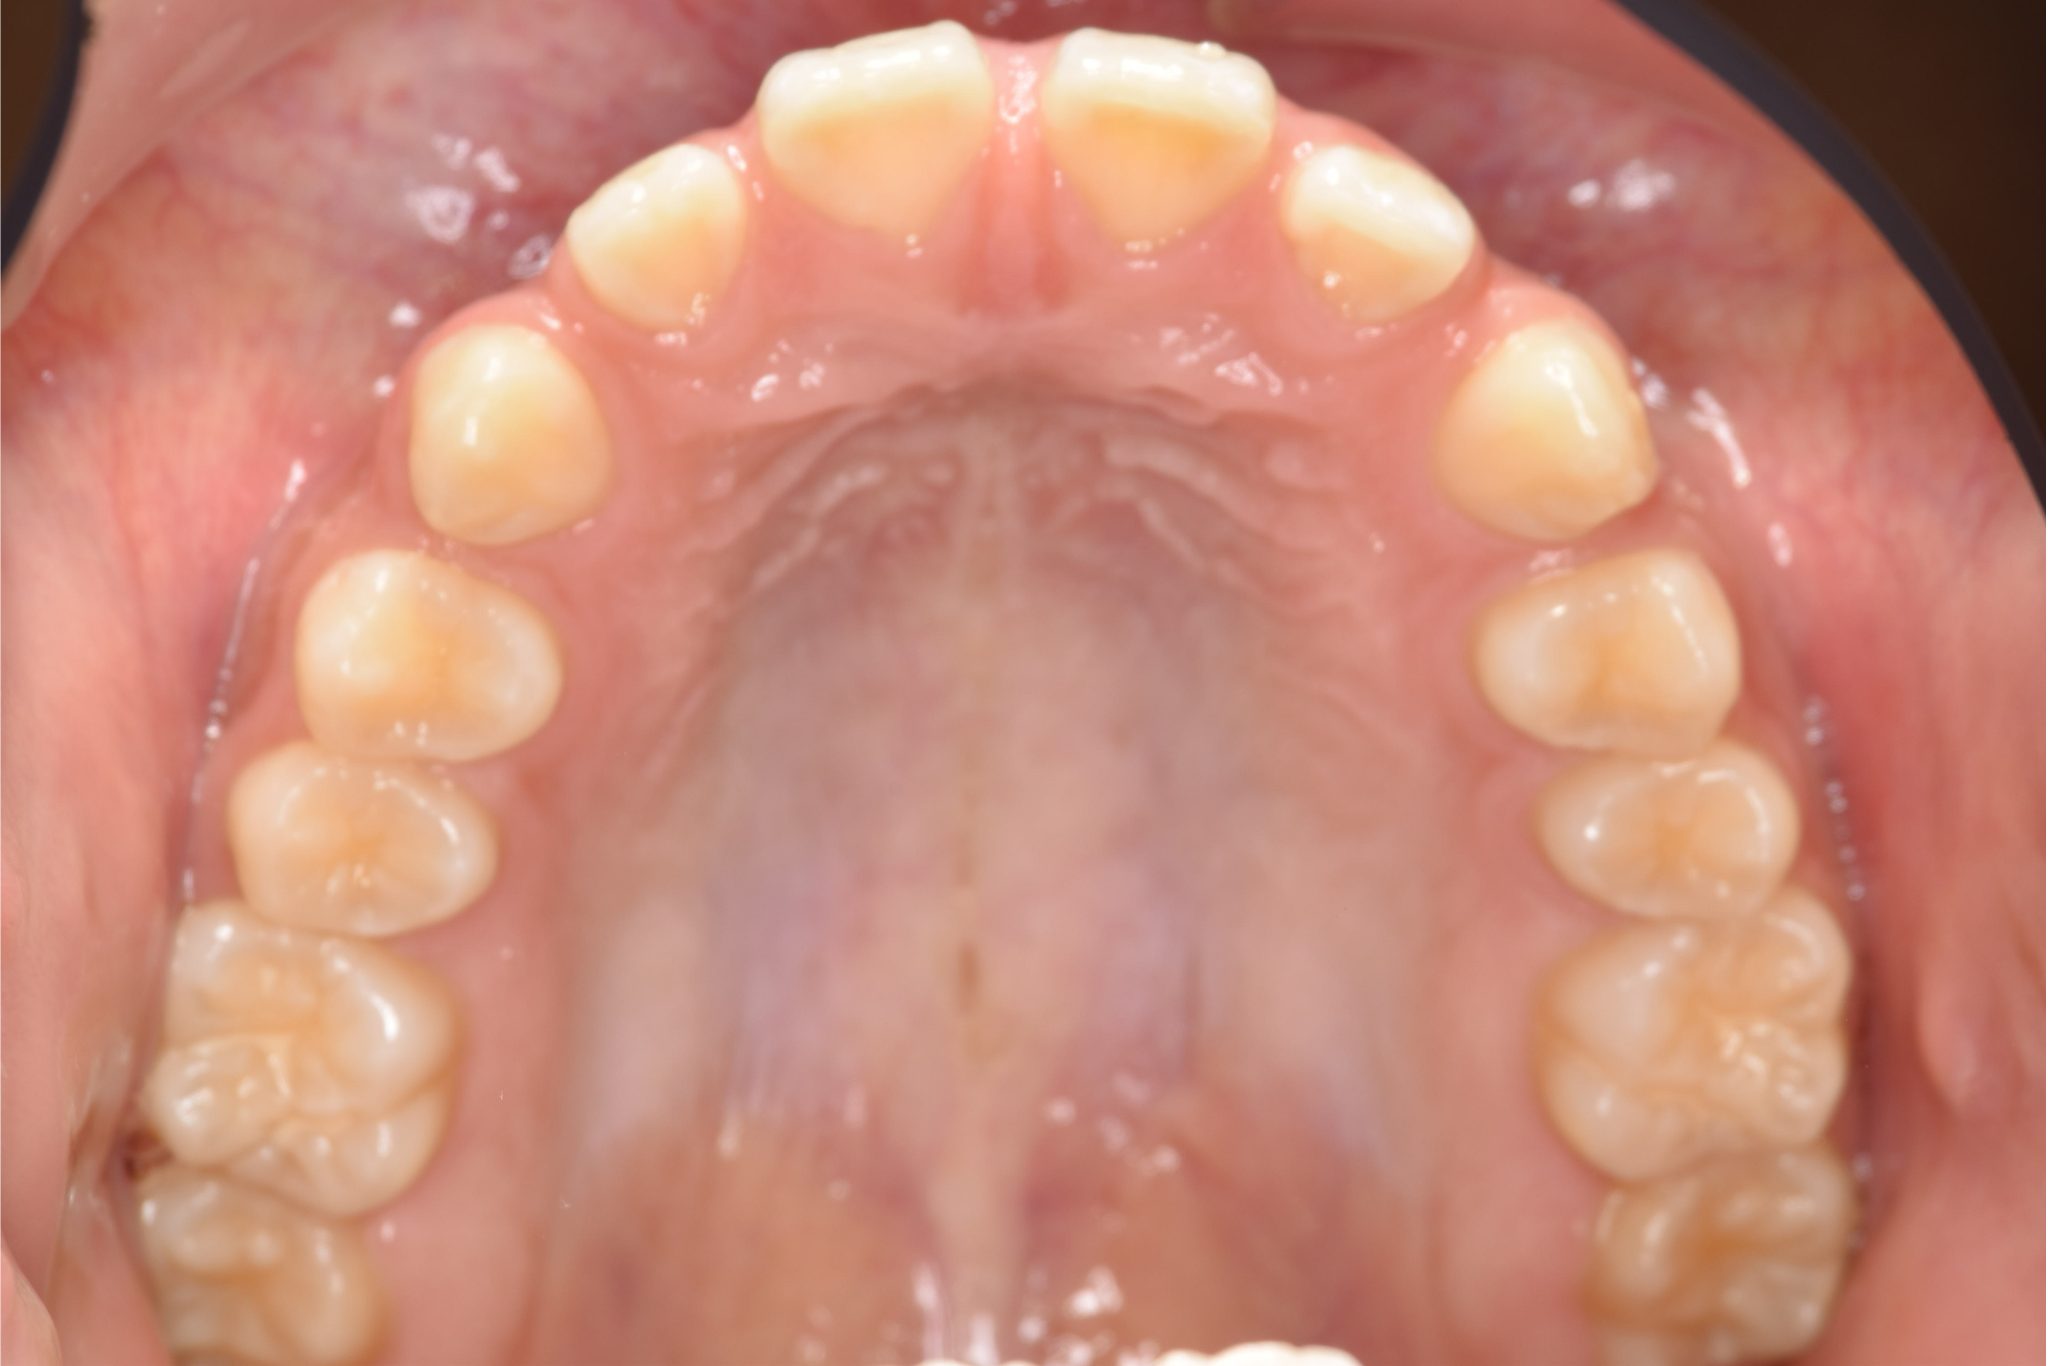

ビフォー

主訴 上前歯が出ている|よく口が開いている

施術内容 上顎急速拡大装置と下顎リンガルアーチを用いて上下顎骨を拡大した。

その後マルチブラケット装置を用いて

非抜歯で歯牙を配列し良好な咬合を獲得した。

鼻閉症状は改善した。

治癒期間 2年10か月間